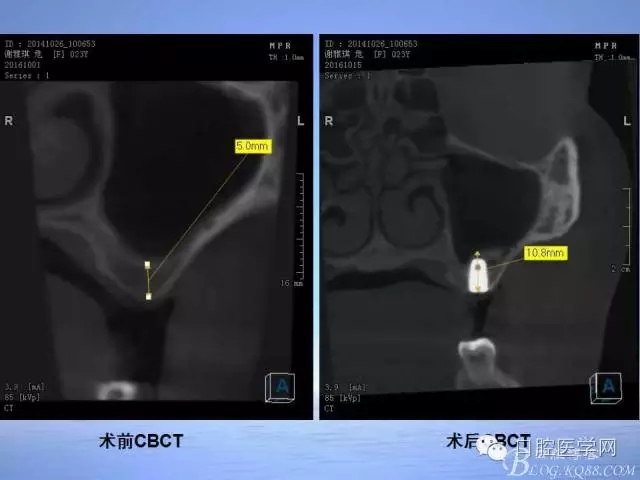

一例CAS-Kit上頜竇內(nèi)提病例